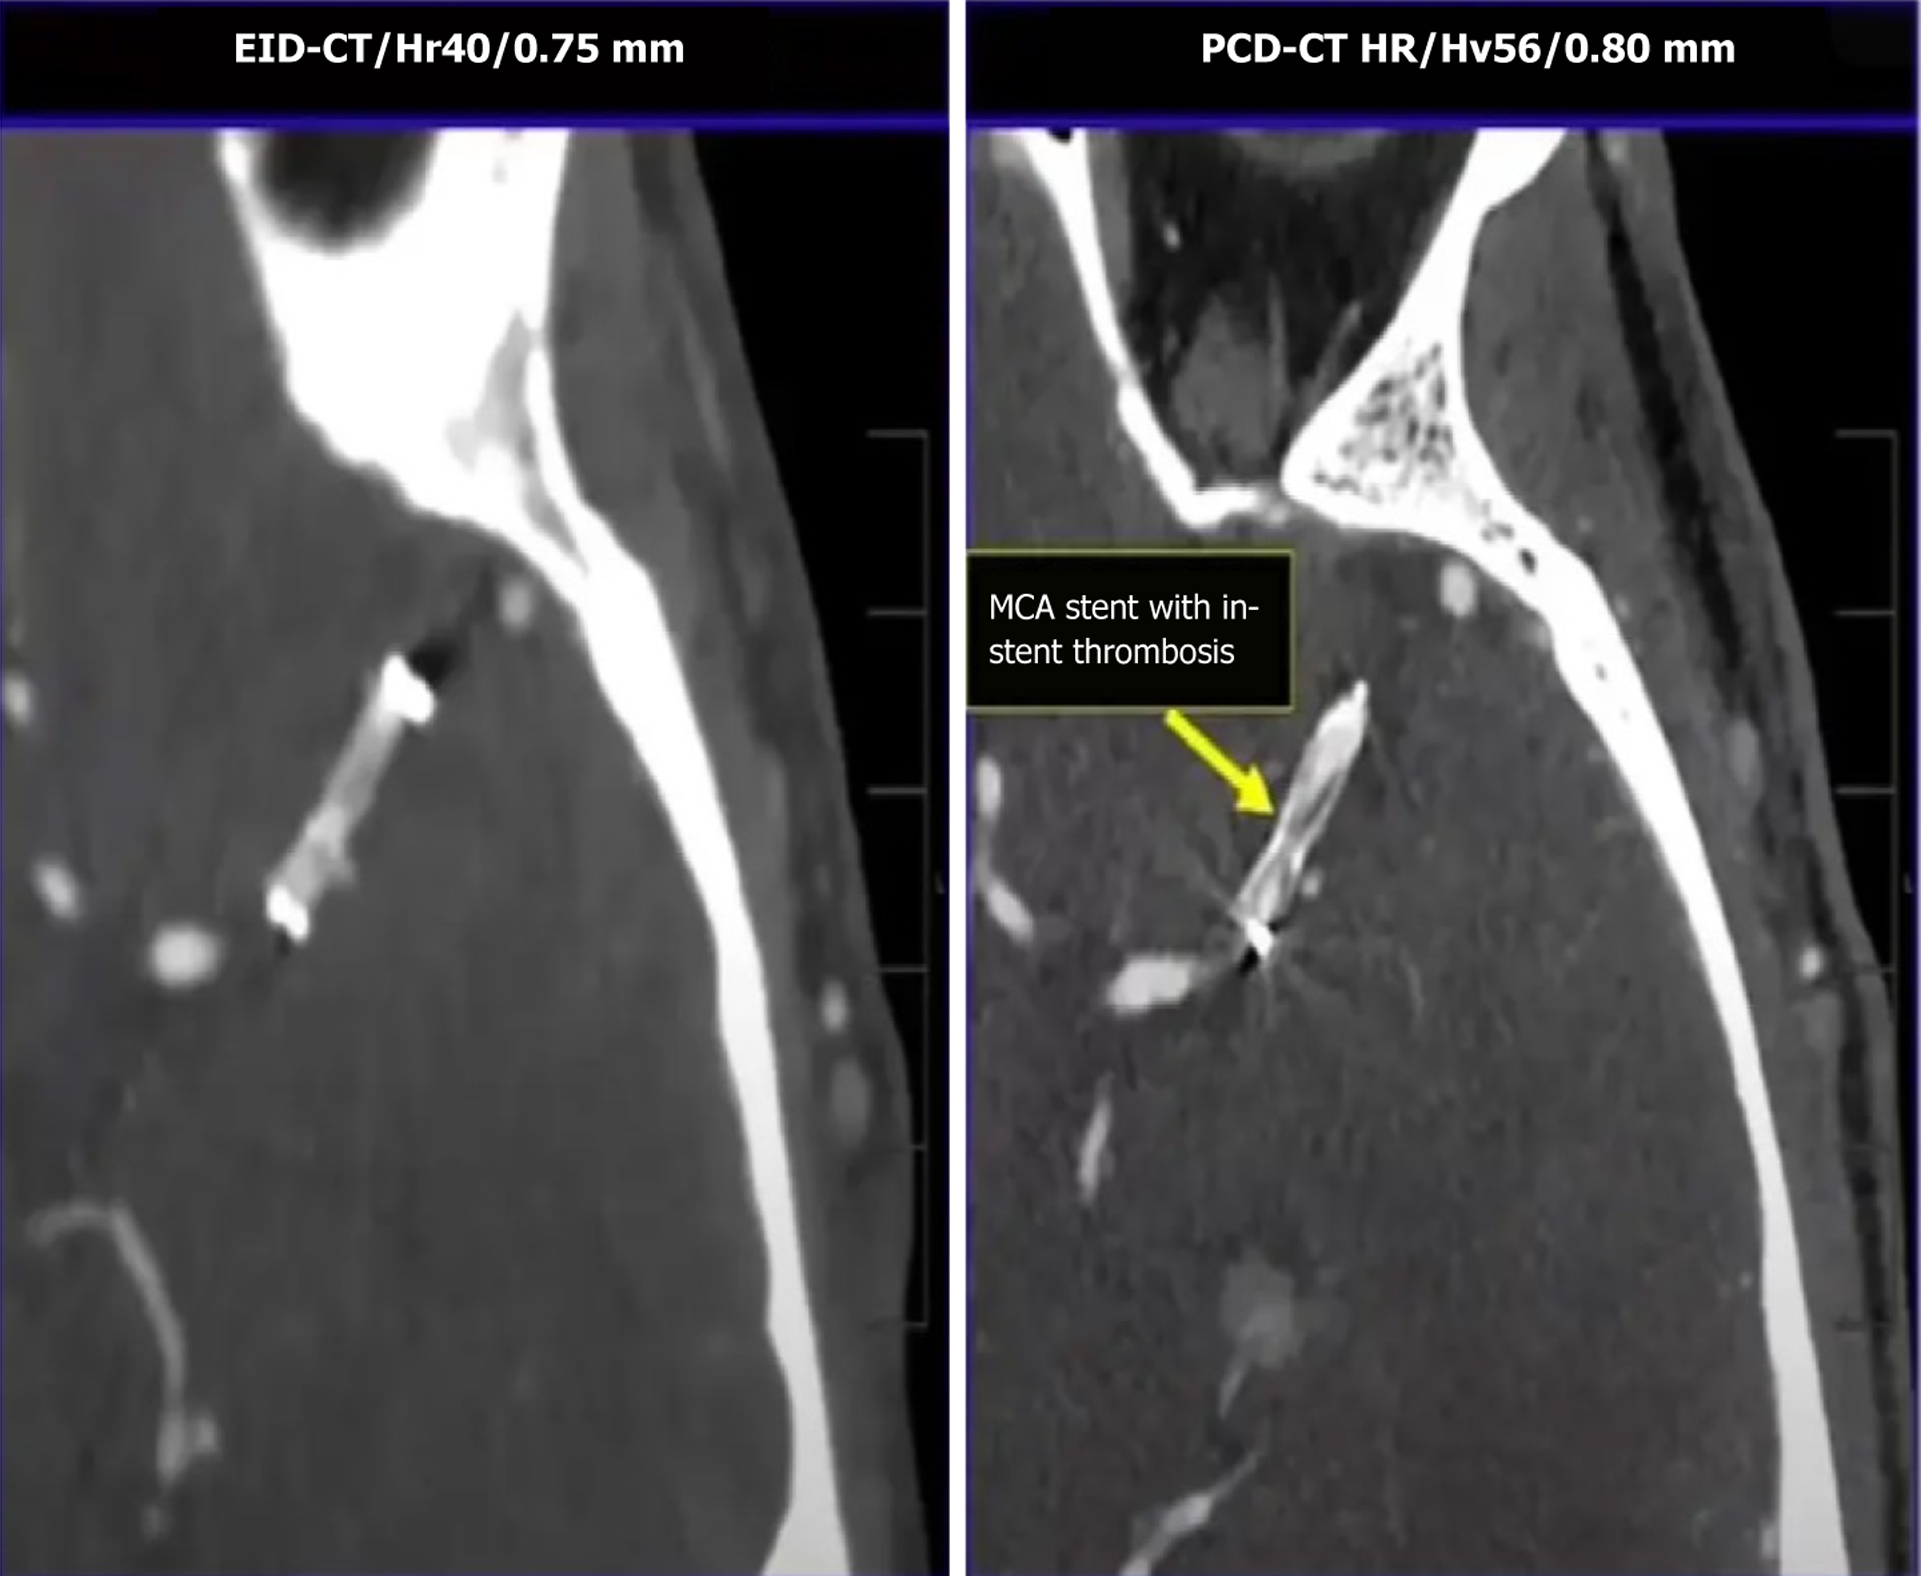

Figure 1 A comparison of traditional energy integrating vs photon-counting detector systems.

A: Energy integrating; B: Photon-counting detector.

Figure 3 Image showing a conventional image of a head computed tomography angiogram (on the left) and its corresponding photon-counting computed tomography version (on the right), which clearly shows a middle cerebral artery stent with in-stent thrombosis.

EID-CT: Energy-integrating detector-computed tomography; PCD-CT: Photon-counting detector-computed tomography; MCA: Middle cerebral artery. Image courtesy of Professor Cynthia H McCollough, Mayo Clinic, Rochester, MN, United States.